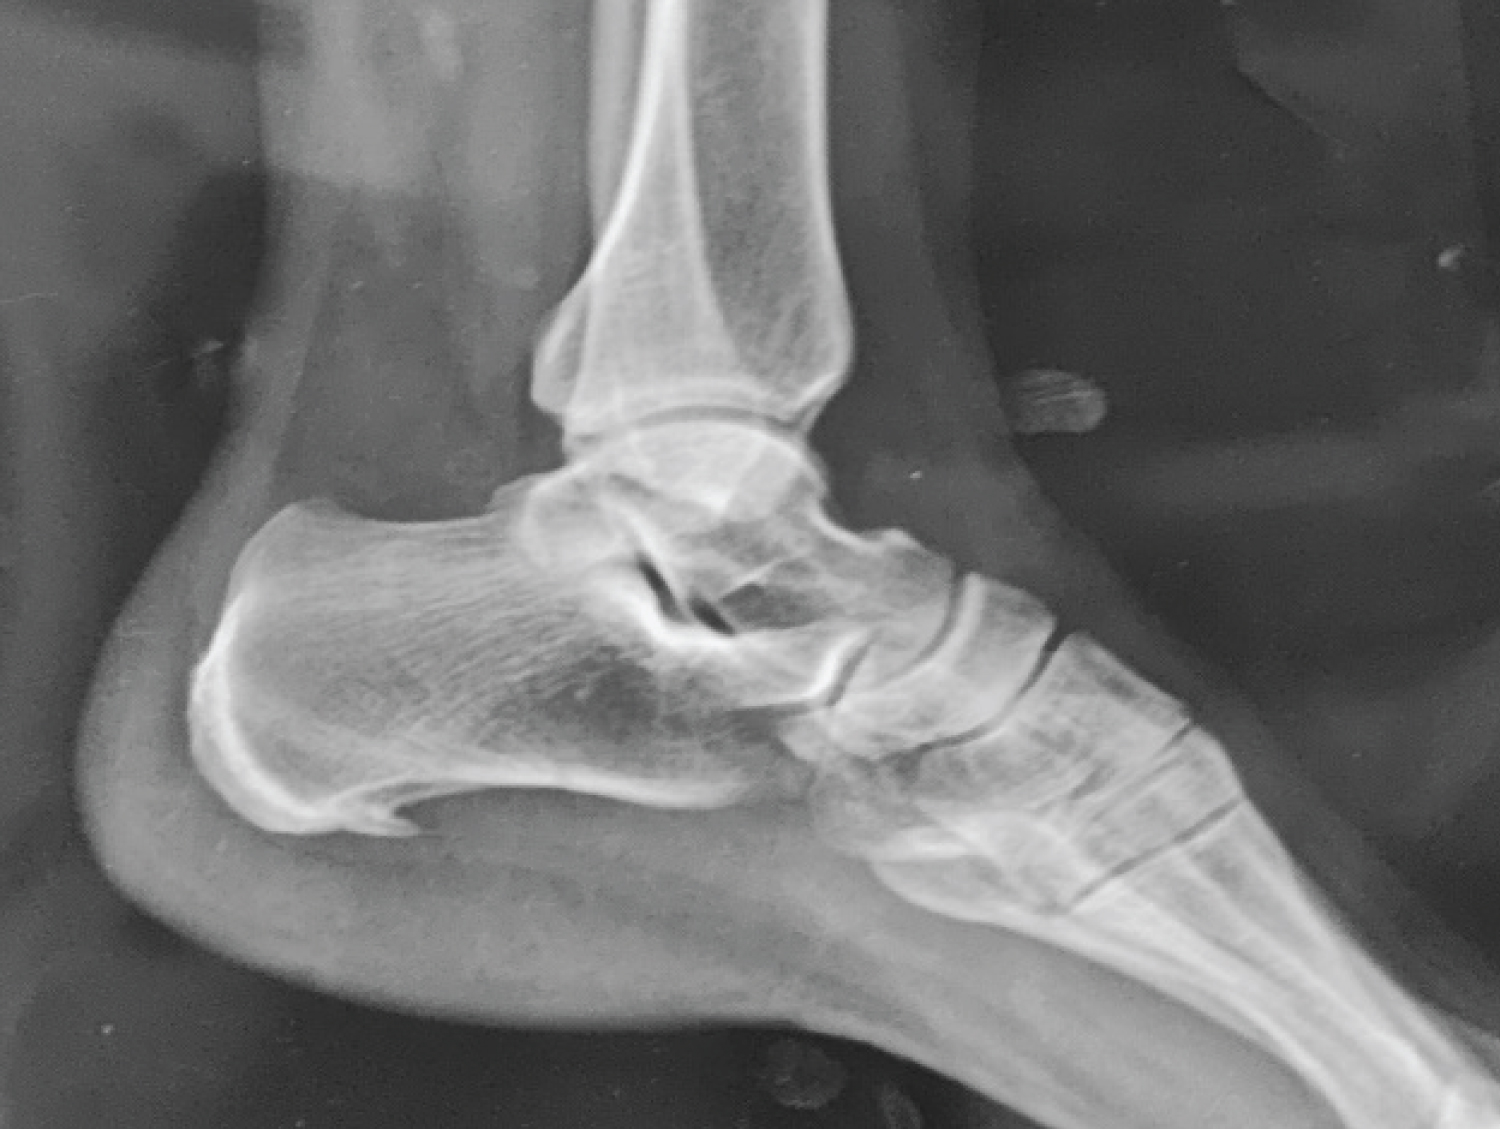

X-rays did not show any bone abnormalities (Figure 1).

Figure 1: Foot X-Ray without ankle anomalies. View Figure 1